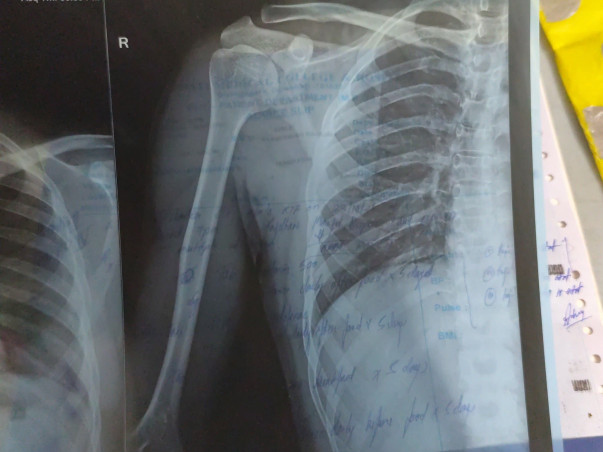

Recently, Palash met with a serious accident, suffering multiple fractures (polytrauma). He is currently receiving medical treatment at Gauhati Medical College Hospital, though he has not yet been admitted.